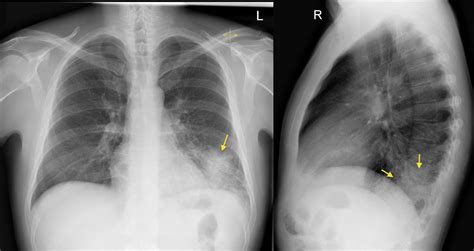

Comparing Lateral and Frontal Chest X Rays

While both Lateral Chest X Ray and frontal chest X-rays provide valuable information, they offer different perspectives. The frontal view is useful for assessing the overall structure and symmetry of the chest, while the lateral view provides depth and positional information. Together, these views offer a more complete picture of the chest's internal structures.

• right lateral chest x ray

• normal lateral chest x ray